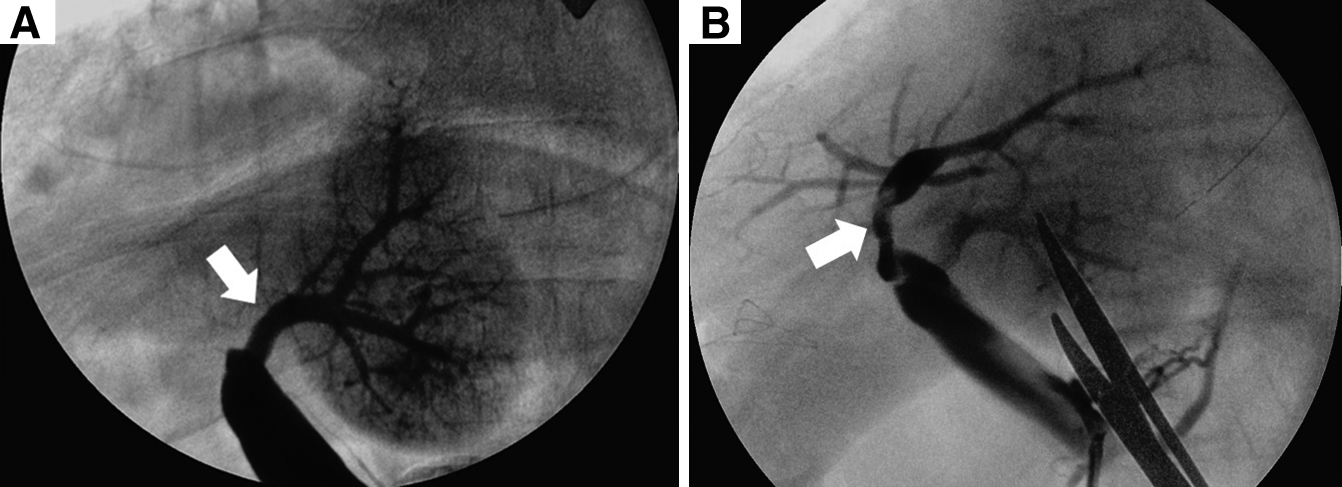

手術所見:右季肋下切開で開腹した.腹水および明らかな遠隔転移は認められなかった.肝円索および肝鎌状間膜を切離して術野を広げ,前方アプローチにより肝右葉切除を行った.肝門部グリソンは個別処理を行い,門脈右前区域枝・右後区域枝は,門脈本幹から十分に離れた位置で門脈左枝が狭窄しないように注意してそれぞれを切断した.具体的には,分岐部から約15 mmのそれぞれの門脈を切断し,断端を連続縫合閉鎖した.肝左葉の脱転は行わなかった.標本摘出後に術中超音波検査を施行したところ,肝左葉の門脈血流が確認されなかった.回結腸静脈から7 Frのシースを留置し門脈造影を行うと,尾状葉枝のみが造影され門脈左枝より末梢は造影されなかった(Fig. 3A).肝右葉のあったスペースに傾いている残肝を左側に戻すと門脈血流の再開が確認されたため,血栓による血流障害ではなく肝左葉がこのスペースへ傾くことに伴う門脈左枝の捻転が原因と考えられた.しかし,残肝を左側に戻したときの再開門脈血流はその位置により変化し非常に不安定であったため,このまま肝円索を腹壁に固定することで肝左葉を固定する方法では不十分と判断した(Fig. 3B).また,門脈の切除・再建による捻転の解消も検討したが,この段階で門脈本幹周囲の剥離は十分でなく,また門脈が余剰とはいえない所見であったため,切除・再建は容易でなく,また確実性は少ないと判断した.以上より,放射線科医師の協力のもと門脈ステント留置の方針とした.先に留置したシースより,門脈臍部から門脈本幹にかけてステントを留置した(Fig. 4).ステントはEpic Vascular self-expanding stent system;10 mm径×40 mm長(Boston Scientific Co.)を使用した.門脈圧格差は計測しなかった.ステント留置後の門脈造影では門脈左枝の血流は十分に再開し,超音波検査でも門脈血流を確認することができた.術後に門脈血栓予防としてヘパリンを注入するため上腸間膜静脈内にカテーテルを留置し,手術を終了した.

(A) Intraoperative portography revealed only the caudate lobe. The left branch of the portal vein was not found. (B) Portography showed torsion and stenosis of the left branch of the portal vein when the remnant liver was turned to the left (arrow).